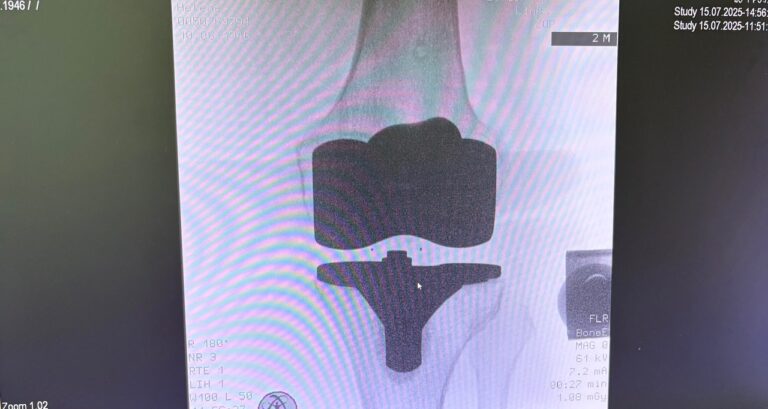

Η ρομποτική αρθροπλαστική γόνατος είναι προηγμένη τεχνική αντικατάστασης γόνατος, όπου ο χειρουργός χρησιμοποιεί ρομποτικό σύστημα υποβοήθησης για εξαιρετικά ακριβή τοποθέτηση των εμφυτευμάτων, βασισμένη στη δική σου ανατομία.

- Προεγχειρητικός σχεδιασμός με CT (συνήθως) → 3D μοντέλο γόνατος

- Καθορισμός ακριβών ορίων κοπών και ευθυγράμμισης

- Το εμφύτευμα τοποθετείται με χιλιοστομετρική ακρίβεια

Η τελική επιλογή της χειρουργικής τεχνικής γίνεται μετά από αναλυτική κλινική αξιολόγηση και προσεκτικό προεγχειρητικό σχεδιασμό, με στόχο το βέλτιστο και ασφαλέστερο αποτέλεσμα για τον ασθενή. Απαραίτητη προϋπόθεση για την επίτευξη εξαιρετικών αποτελεσμάτων αποτελεί η εξειδίκευση του χειρουργού στη συγκεκριμένη τεχνική, καθώς και η εκτεταμένη εμπειρία με μεγάλο αριθμό επεμβάσεων. Ο έμπειρος ορθοπαιδικός χειρουργός κ. Νικόλαος Καλύβας εφαρμόζει την ρομποτική τεχνική σε μεγάλο αριθμό χειρουργείων.